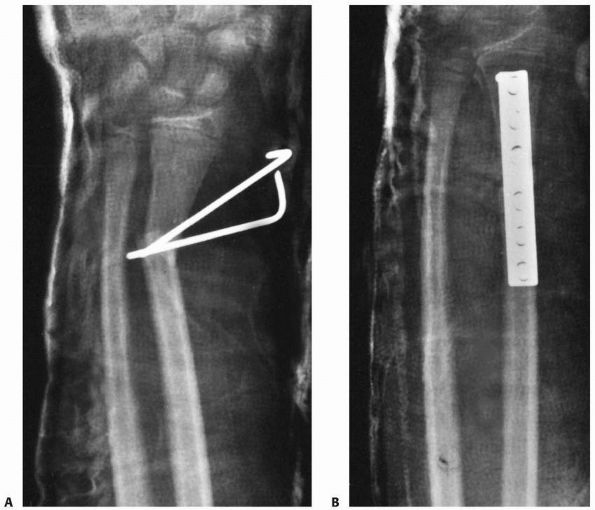

tissues. The distal fragment of epiphysis and metaphysis often is in

bayonet apposition with the proximal fragment. Concomitant radial and

ulnar fractures at the same level may be more unstable than isolated

fractures.244 However, Gibbons et al.80

reported loss of reduction in 91% of isolated radial fractures after

closed reduction. Although a rare fracture with bayonet apposition in a